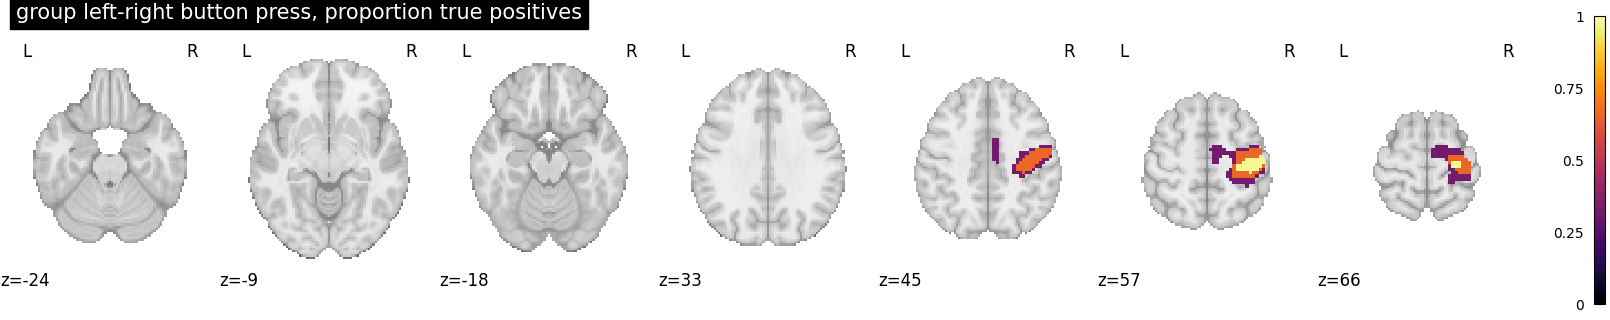

We threshold the second level contrast at uncorrected p < 0.001 and plot

proportion_true_discoveries_img = cluster_level_inference(

z_map, threshold=[2.5, 3.5, 4.5], alpha=0.05

)

cut_coords = [-24, -9, -18, 33, 45, 57, 66]

plot_stat_map(

proportion_true_discoveries_img,

threshold=0.0,

display_mode="z",

vmax=1,

cmap="inferno",

title="group left-right button press, proportion true positives",

cut_coords=cut_coords,